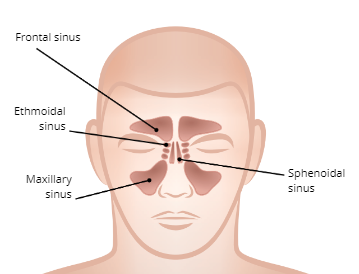

SInuses

four pairs of hollow spaces in the skull that open into the nasal cavity

Functions of the Sinuses

1. Moistens and filters air

2. Regulate air temperature

3. Provide voice resonance